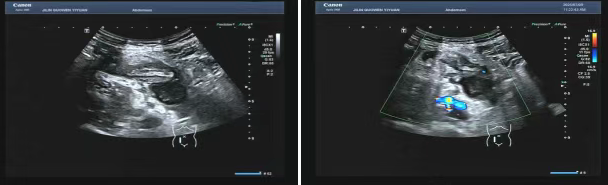

80 歲的張爺爺(化名)因前列腺增生前往國(guó)文醫(yī)院就診,泌尿外科為其開具了泌尿系超聲檢查。超聲科醫(yī)生在檢查過(guò)程中,憑借敏銳的觀察力,發(fā)現(xiàn)患者右下腹有異?;旌匣芈暟鼔K。醫(yī)生沒(méi)有放過(guò)這一異常,立即展開進(jìn)一步探查,結(jié)果顯示包塊內(nèi)疑似有闌尾結(jié)構(gòu),且周圍組織存在粘連,還伴有液性暗區(qū)。考慮到老年患者病情往往較為隱匿,癥狀也不典型,醫(yī)生第一時(shí)間與臨床醫(yī)生溝通,建議進(jìn)行緊急處理。隨后,經(jīng)過(guò)臨床醫(yī)生詳細(xì)檢查,患者迅速辦理住院并接受手術(shù),術(shù)后病理檢查結(jié)果確診為 “闌尾壞疽伴穿孔合并膿腫形成”。

主治醫(yī)生介紹,老年人患闌尾炎時(shí),癥狀常常不典型,很容易被誤診為腸胃炎或其他疾病。張爺爺僅表現(xiàn)出輕微腹脹的癥狀。倘若不是超聲檢查時(shí)意外發(fā)現(xiàn),極有可能延誤治療,進(jìn)而引發(fā)感染性休克,甚至危及生命。超聲檢查在這類急腹癥的篩查中,發(fā)揮了至關(guān)重要的作用。